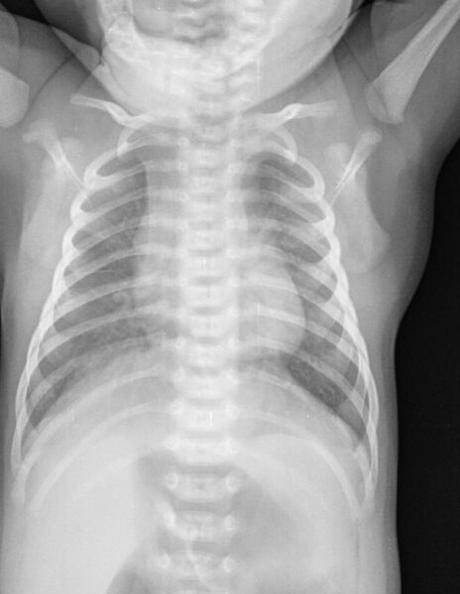

Silueta cardiomediastinica de forma habitual para la edad.

Tráquea central, columna vertebral central.

Hilios pulmonares, de aspecto adecuado.

Campos pulmonares, con presencia de imágenes que simulan ser micronódulos.

Recesos cardiofrénicos y costo frénicos se observan libres.

Estructuras óseas, sin evidencia de lesiones líticas, blásticas o perdidas de la contigüidad. Fisis de crecimiento acorde a la edad.

EN EL PRESENTE ESTUDIO RADIOGRÁFICO, CON IMÁGENES SUGERENTE DE BRONQUIOLITIS.